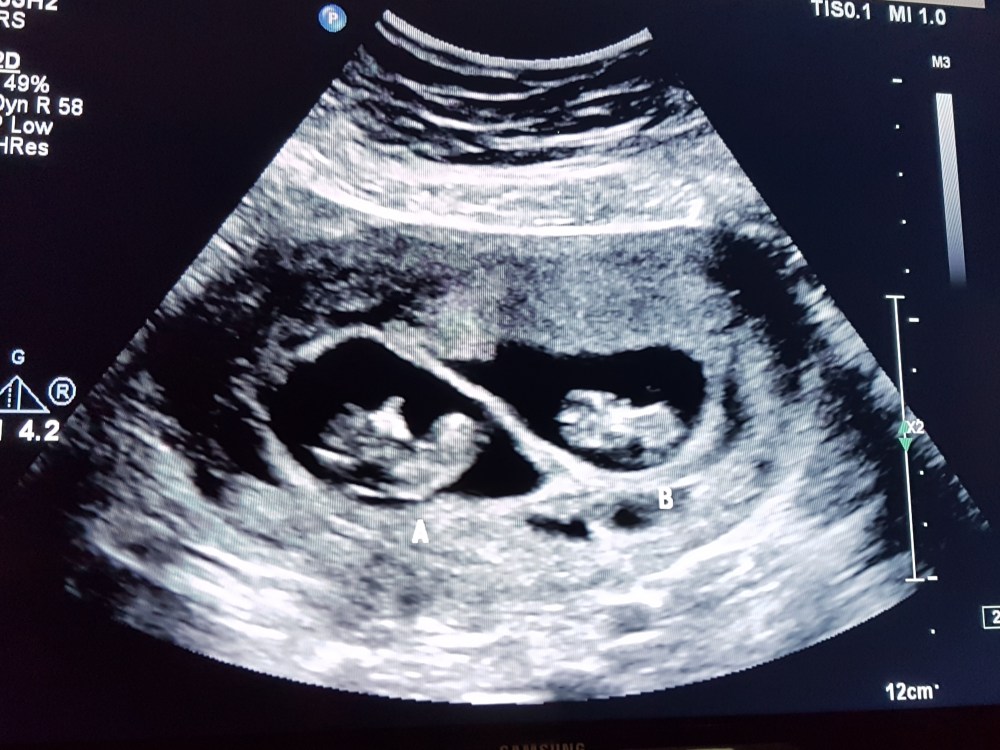

I took it in person on my cell phone, but this is probably still the best photo I’ve ever seen.

Our twins are expected to arrive by Pelican early in 2019.

Twins. Two beautiful little humans will be joining our family. As utterly thrilled as we are, I’ll be forthcoming and admit there are times that it still doesn’t seem quite real, that we should be granted a blessing of this immensity, but it’s really, honestly happening. We are referring to our babies as “The Sprouts” for now; I like the sense of new life and great potential in their nicknames.

The babies are fraternal twins. Fraternal twin pregnancies are safer in several ways, especially for the babies, since they have separate amniotic sacs and placentas. It’s rather like living in two separate halves of a duplex rather than being immediate roommates. At last week’s ultrasound, Twin A had a heartbeat of 170 beats per minute, and was grooving around, while Twin B was more relaxed with a heart going 161 beats per minute.